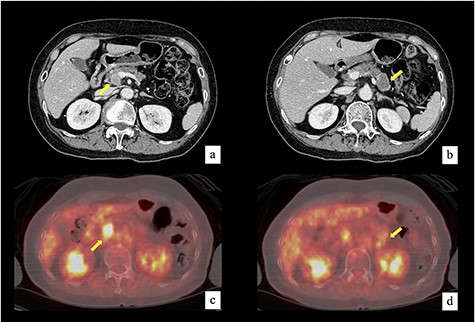

A 77-year-old woman with a solitary existence was referred to our hospital for the treatment of pancreatic tumors. All hematologic examinations including tumor makers were within the normal ranges. Contrast-enhanced abdominal computed tomography revealed an 18-mm mass in the pancreatic head that had invaded the right side of the SMV and a 32-mm mass in the pancreatic tail (Fig. 1a and b). Fluorodeoxyglucose (FDG) positron emission tomography showed the accumulation of FDG in both masses (Fig. 1c and d). No metastatic lesion was found in these images. Endoscopic ultrasound-guided fine-needle aspiration revealed that both masses were adenocarcinoma. Of course, TP was appropriate procedure for these pancreatic carcinomas; however, parenchyma-preserving pancreatectomy was considered due to the patient’s age and postoperative quality of life with a solitary existence. Preoperative computed tomography showed the dorsal pancreatic artery (DPA), which flowed into the pancreatic body (Fig. 2a and b). If it was possible to preserve the DPA and confluence of the splenic vein (SpV), preservation of middle segment pancreas was considered possible.

Contrast-enhanced computed tomography revealed an 18-mm mass in the pancreatic head that had invaded the right side of SMV (a) and a 32-mm mass in the pancreatic tail (b). FDG positron emission tomography showed the accumulation of FDG in both masses. The maximum standardized uptake value was 12.9 in the pancreatic head mass (c) and 3.0 in the pancreatic tail mass (d).